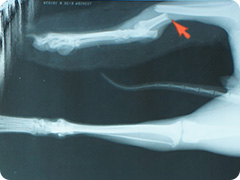

- 骨折

- 高いところから飛び降りたりすることで骨折することがあります。骨折した足はぶらーんとして床に足を付けられない状態になります。

創外固定法による治療

プレートを用いた治療